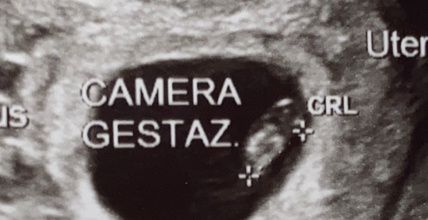

2202 giorni faBuongiorno a tutte... mi date un vostro parere.? Secondo voi sarà un maschio o una femmina.? Questa è l’eco della tn Questa invece è l’eco .4d della 7 settimana Nn vedo l ora di leggervi

2206 giorni faSecondo voi è un maschietto o una femminuccia.? Vi mostro il turbercolo ( credo si chiami così )